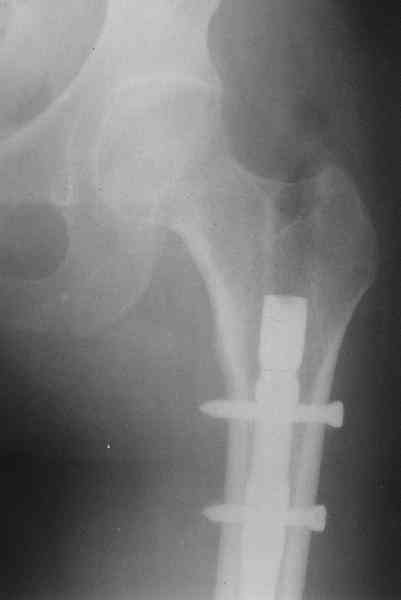

Оперирована в январе 2007 года по выходе из комы и восстановления витальных функций. Накостный остеосинтез DCP-LC. Снимки прилагаются.

Через 4 месяца стали беспокоить боли и деформациябедра. На снимке угловая деформация AP - варус 11 град.; lateral - 29 град. Объем движений в коленном суставе: ограничение сгибания до 90 град. Локально - патологическая подвижность в нижней трети бедра. Локальная гипертермия, отек мягких тканей. Гиперемии нет. Передвигалась на костылях.